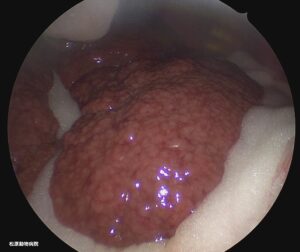

画像:腹腔鏡下で観察している肝臓。辺縁が鈍化し、肝腫大が疑われる。

画像:腹腔鏡下で観察している肝臓。表面は不整に萎縮し、肝硬変が疑われる。